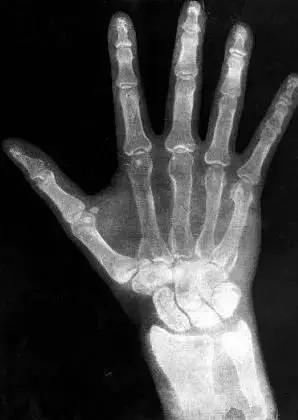

3.X光:屏幕上意外看到自己手掌骨骼 惊呆物理学家

世界科学史十大“最意外发明”(图3)

1895年的一天,德国物理学家威廉·伦琴在德国维尔茨堡大学的实验室中忙碌地研究阴极射线管的特性时,突然注意到一束光投射到了屋内另一头的氰亚铂酸钡荧光纸板屏幕上,接着他发现纸板屏幕上出现了一只形同骷髅的手掌骨骼,他最初的惊讶顿时变成了震惊。

伦琴很快意识到,一些神秘的辐射光不但穿过了空气、并且穿过了他的血肉,从而使他的手掌骨骼投影在了光线暗淡的纸板屏幕上。这种光的粒子显然能够穿过固态物体,伦琴接着发现,他可以借助这种超乎想像的辐射光来产生清晰的体内图像。就这样,世界上第一幅X光片诞生了。X光之所以叫X,是因为X是未知事物的代称。没多久,世界各地的科学实验室都开始复制出X光机,20年后,X光开始大量用于医学目的。由于X光是大自然的一种现象,所以准确地说,伦琴是意外发现了X光,而不是发明了X光。